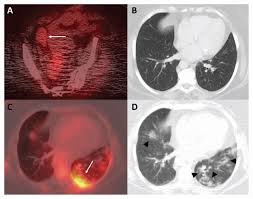

최첨단 현대의학으로 가장 적절한 방법이 양전자단층촬영술(Positron Emission Tomography, PET)이라고 나는 생각한다. PET는 체내 대사 변화를 촬영하는 기기로 CT나 MRI 다음에 개발된 영상장비이라고 한다.

요즘은 여기에 CT를 붙여서 PET 영상과 CT 영상을 융합해 서로 약점을 보완해 검사의 질을 더욱 높이고 있다고 한다.

여기에 방사성 핵종 F-18를 붙여(F-18 FDG라고 함) 혈관 주사하면 빨리 자리는 암세포는 포도당이 더 필요해 정상 세포보다 10∼100배 더 많이 모여들고 이를 방사능으로 촬영해 찾아낸다. 암이 1㎝만 돼도 10조개의 암세포가 있어 CT, MRI 소견이 애매한 경우 유용하게 쓰인다.